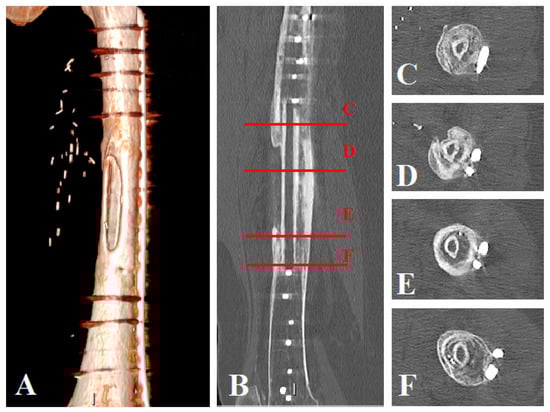

Full weight-bearing was achieved early (11 weeks (8–12)), with physiotherapy involving progressive weight-bearing, which was allowed postoperatively, while keeping the patient’s pain in mind. We assumed that fibula fusion, seen on CT scans but not necessarily on standard X-rays, may have facilitated this process. Bone healing was observed earlier on the first postoperative CT scan than on standard X-rays; CT scans performed earlier in the follow- up could have revealed better fusion times in our patients.

The “Capasquelet” can be considered a method of choice for bone defects extending into the femur, particularly in complex cases requiring two-stage management; it might also be proposed in tibial resections. In the literature, the combination of several types of techniques appears to result in fewer complications, thus providing a cumulative advantage, and in tumor cases, it avoids long and harrowing one-stage surgeries [,,,,,]. Obtaining an osteoinductive membrane promotes bone consolidation and management of septic contexts. This osteoinductive membrane needs to be preserved for the second stage, and it should only be incised and not excised []. The placement of an allograft and a vascularized fibula in this induced membrane after cement removal is straightforward, with an easy workspace preserving reconstruction placement. It may allow primary (allograft compression) and secondary mechanical stability (fibula fusion) (Figure 5).

Figure 5.

Patient No. 1 CT scan control at 14 months postoperatively: (A) CT scan 3D reconstruction of the healed allograft; (B) sagittal plane view with axial view level representation: (C–F) (C) axial view of the proximal host femur with the healed fibula graft, (D,E) axial views of the healed fibula graft in the allograft, (F) axial view of the distal host femur with the healed fibula graft.